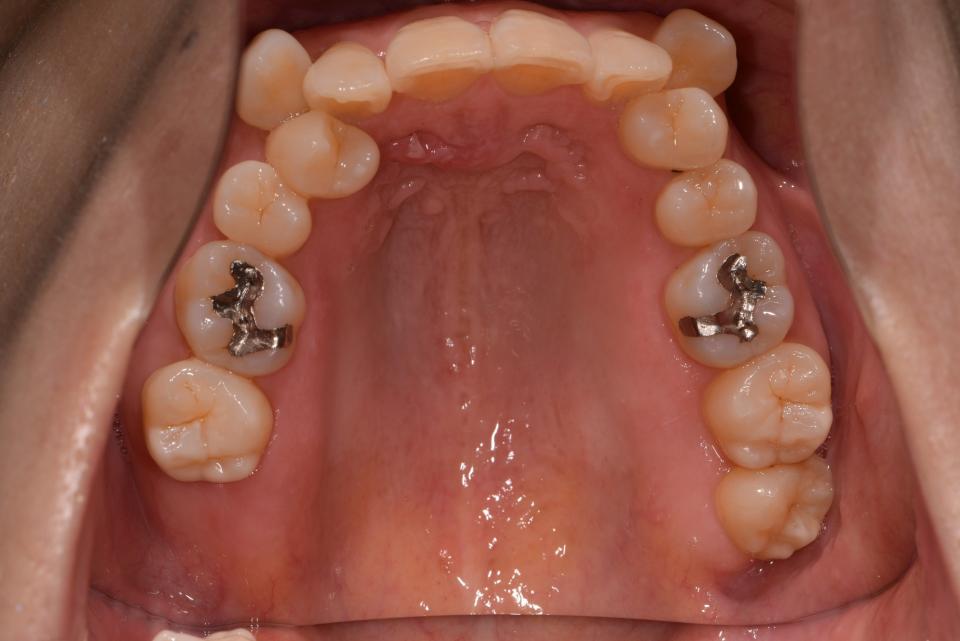

矯正治療前

40代女性の患者さんです。

八重歯が気になり矯正治療を始めました。

上の左右4番目の抜歯をして、マウスピース型の矯正治療装置を使用し、歯のやすり掛け(IPR)を行いました。